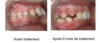

Kalvin, avant/après traitement